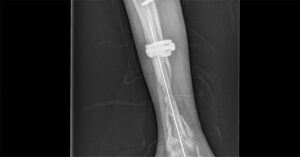

Based on the 3D reconstructed model, the tibial prosthesis was printed using MAGIC-HT-PRO and the surgeon performed the replacement prosthesis surgery as seen in the figure.

Post-operative data (orthotropic)

Post-operative data (lateral)